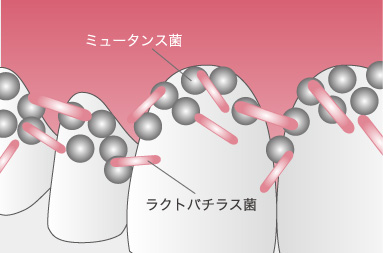

むし歯は、細菌(むし歯菌=ミュータンス菌・ラクトバチラス菌)が糖分を元に作り出した酸が歯を溶かすことによって生じます。ミュータンス菌はむし歯を作り、ラクトバチラス菌はそれを進行させます。ミュータンス菌は、だ液から感染してしまいます。

ミュータンス菌

ラクトバチラス菌

ミュータンス菌とは、食事に含まれている糖から酸を作り出す菌です。その酸によって歯が少しずつ溶けてしまいます。また、糖のない状態でも酸を作ることができ、砂糖からネバネバとした、水に溶けない物質を作り出し、歯に付着し、他のくっつく力のない細菌を巻き込んでバリヤーのようなものを作り出して、悪玉細菌の巣となる「バイオフィルム」を形成します。

ラクトバチラス菌とは、ミュータンス菌と供に働くことによって、口腔内にむし歯を作り出し、より拡大していく菌です。ミュータンス菌の働きによって、むし歯のきっかけができます。ミュータンス菌には、歯の表面に付着する能力があり、エナメル質を溶かしてむし歯を作ります。

そして、そこへラクトバチラス菌が入り込み、むし歯を拡大していきます。ラクトバチラス菌には、歯に付着する能力がありませんが、ミュータンス菌の作ったむし歯の中に、住み着くことが出来ます。